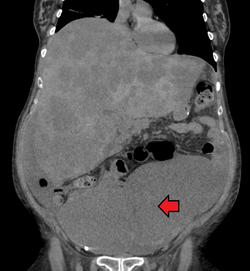

Colon cancer with extensive metastases to the liver

A colorectal cancer is sometimes initially discovered on CT scan.[81]

Presence of metastases is determined by a CT scan of the chest, abdomen and pelvis.[20] Other potential imaging tests such as PET and MRI may be used in certain cases.[20] MRI is particularly useful to determine local stage of the tumor and to plan the optimal surgical approach.[81]